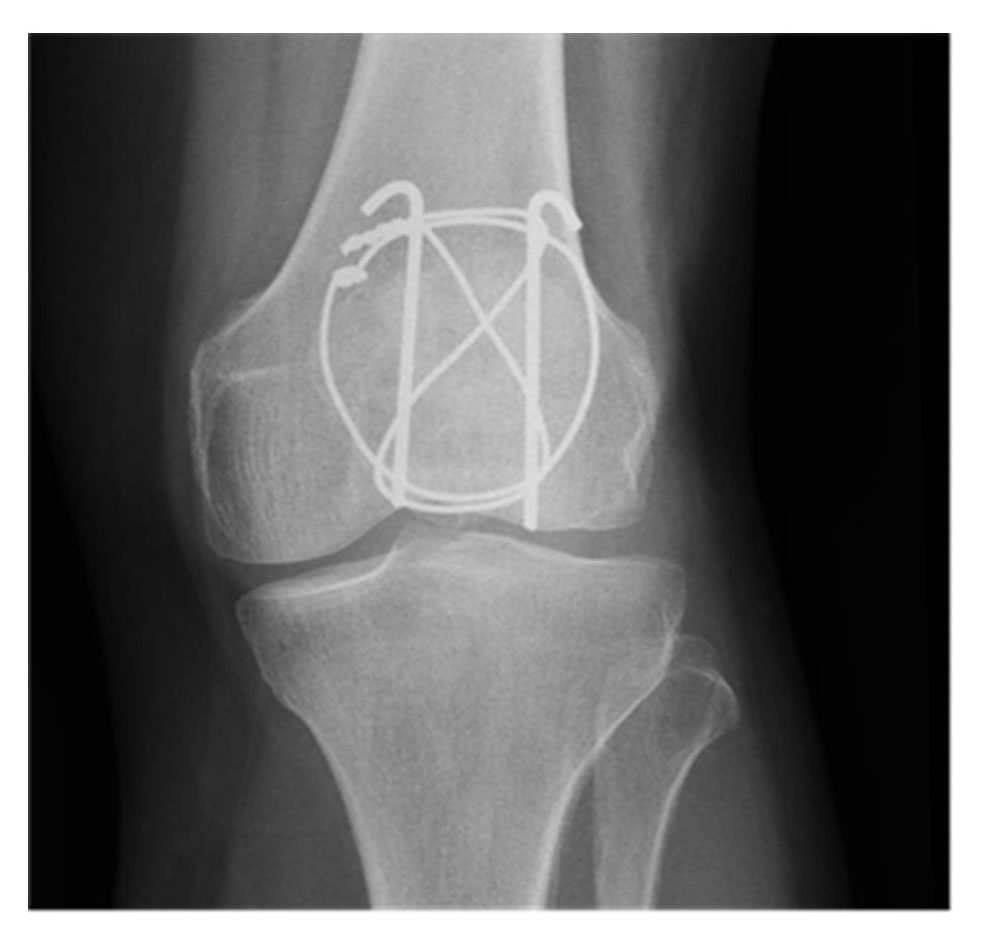

The most commonly used method is a tension band technique; however, this is only possible after a more complex fracture has been converted into a two‐part fracture and if there is no discontinuity on the articular side. Additional fracture fragments can be fixed using supplementary circular wire (fig. 4) [16] or mini‐fragment screws (fig. 5) [17]. The repair of the retinacular defect contributes also to the overall stability of the construct.

Figure 4 Tension band construct reinforced with an equatorial wire (CHUV).